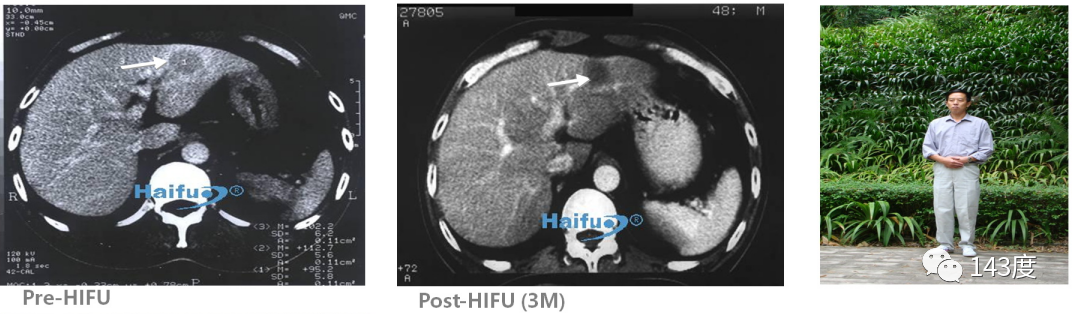

Liver Cancer Treatment Case 1:

Patient: Male, primary liver cancer

World’s first HIFU treatment for liver cancer, survived for 12 years.